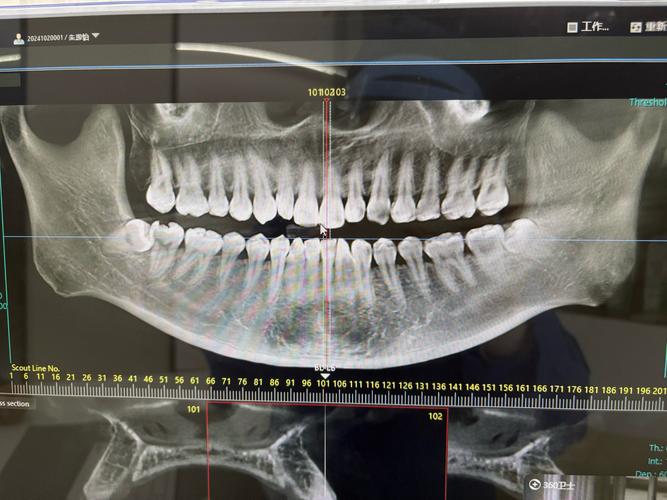

- CBCT(锥形束CT):是口腔专用三维CT,能1:1还原牙槽骨的立体结构,像给骨头“拍了张高清3D照片”,可精确测量骨高度(误差≤0.1mm)、宽度、密度,同时清晰显示下颌神经管、上颌窦、鼻腔等重要解剖结构的位置,避免种植时损伤。

举个例子:如果缺牙位置下方有下颌神经管,全景片可能只显示一个模糊的“白线”,但CBCT能精确显示神经管的直径、走向与牙槽骨的距离,医生就能提前规划种植体植入的角度和深度,避免碰到神经(否则可能导致下唇麻木)。

CBCT是种植前评估骨量的“金标准”,也是制定个性化种植方案的基础。

拍完CT后,医生会通过专业软件(如Dexis、ImplantStudio)进行三维重建,在电脑上“模拟”种植过程:

- 测量骨量:精确标记缺牙位置的骨高度、宽度,计算能否满足种植体直径(常用3.5-5.0mm)和长度(8-16mm)的需求;

- 设计种植路径:避开神经管、上颌窦等重要结构,确定种植体植入的角度、深度;